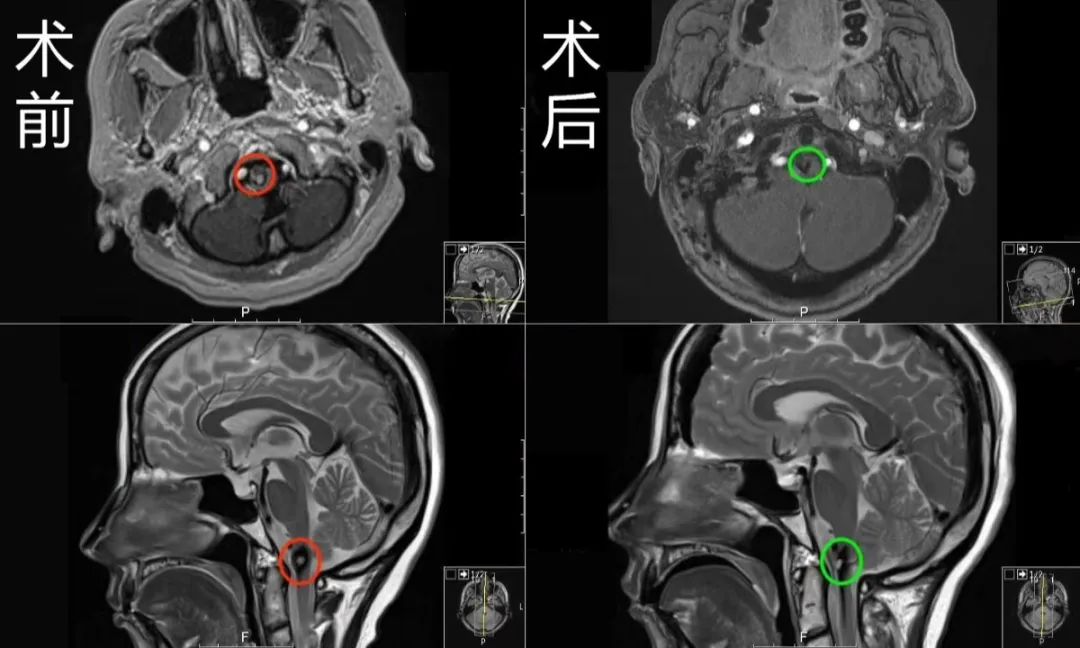

6.40多岁张先生,脑干海绵状血管瘤

40多岁的张先生患脑干海绵状血管瘤,保守治疗后发生2次出血,视力下降、视野缺损。医生告诉他和家属:脑干出血严重,有生命危险。幸运的是,张先生争取了2019年INC巴特朗菲教授国内示范教学手术,较终从“濒临死亡”到“终身治愈”,现已恢复正常生活。

“当时国内的医生看完我的病情,觉得手术风险大,造成的后遗症会比较严重,当时是国内的医生这么描述的,当时我们想因为我的症状还不是的严重,所以我们想就是说再观看一下,但是呢就是有机会认识了巴教授以后呢 ,巴教授给到我的治疗建议,详细的说了他能够帮我做手术,以及手术对我后面生活的影响,这给了我很大信心,我决定就是说还是请巴教授来做这个手术,对手术效果满意,从生活质量来说的话,得到了好的恢复,巴教授的手术还是让我得到了很多的益处。”——张先生